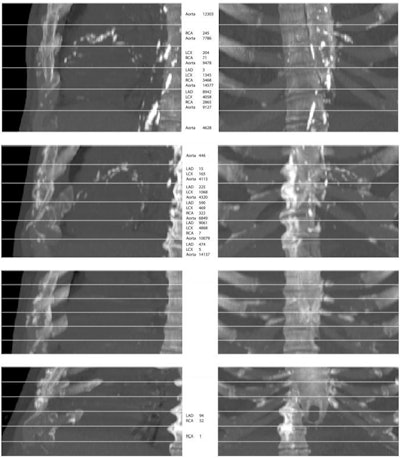

From top to bottom, maximum intensity projections (MIPs) of four randomly selected images from the evaluation set. The top two rows show cases that contain extensive arterial calcification (mainly the aortic arch), and the bottom two rows show controls containing none or limited arterial calcification. The left and right columns show MIPs of respective sagittal views and coronal views. The middle column lists Agatston scores if present in the slab. Note that none of the examples contained valve calcifications. Images have been automatically aligned such that they mimic the field of view of cardiac CT. However, for visualization purposes, large parts of the ribs and the vertebrae have been manually cropped. LAD = left anterior descending artery, LCX = left circumflex artery, RCA = right coronary artery. Images and caption courtesy of the RSNA.